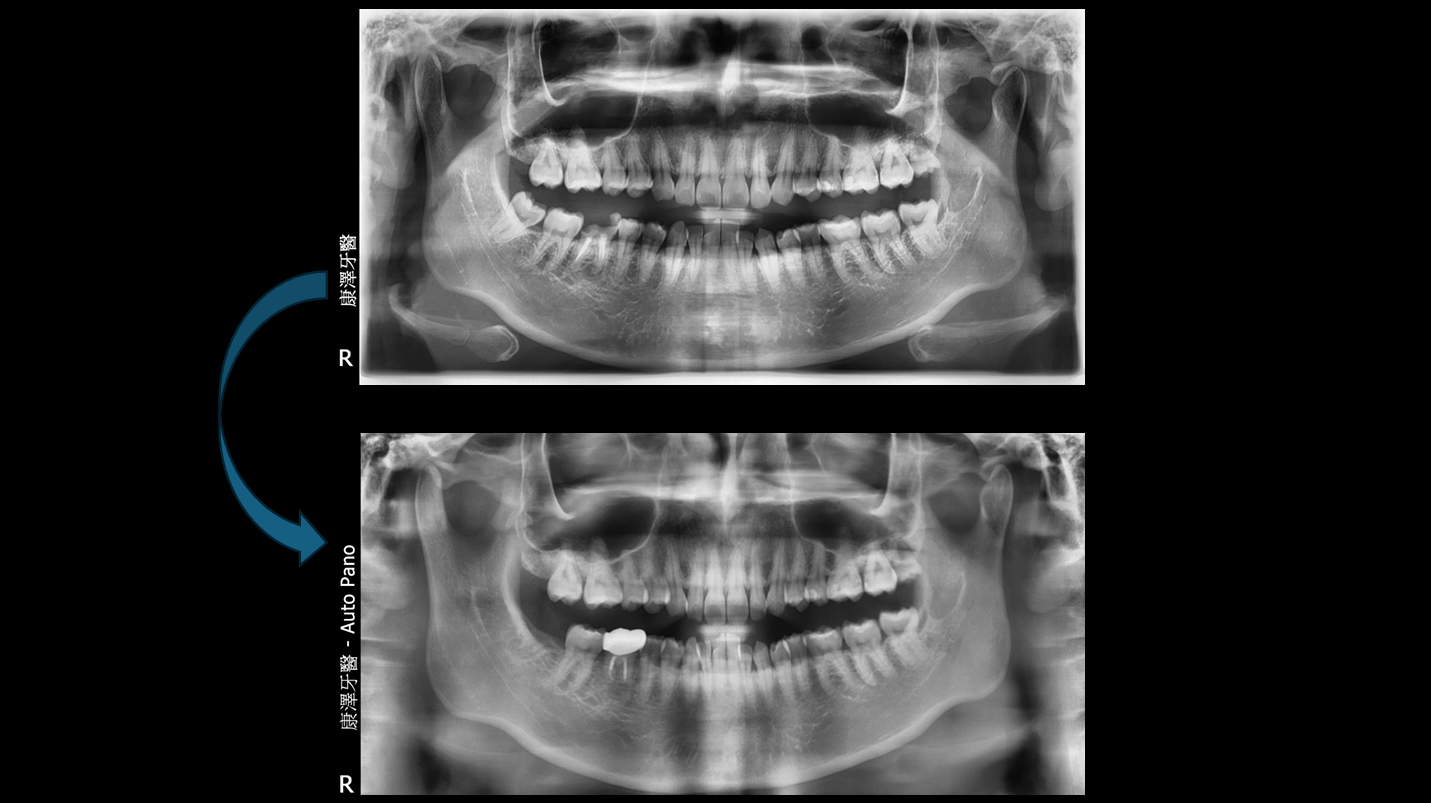

術前

術後